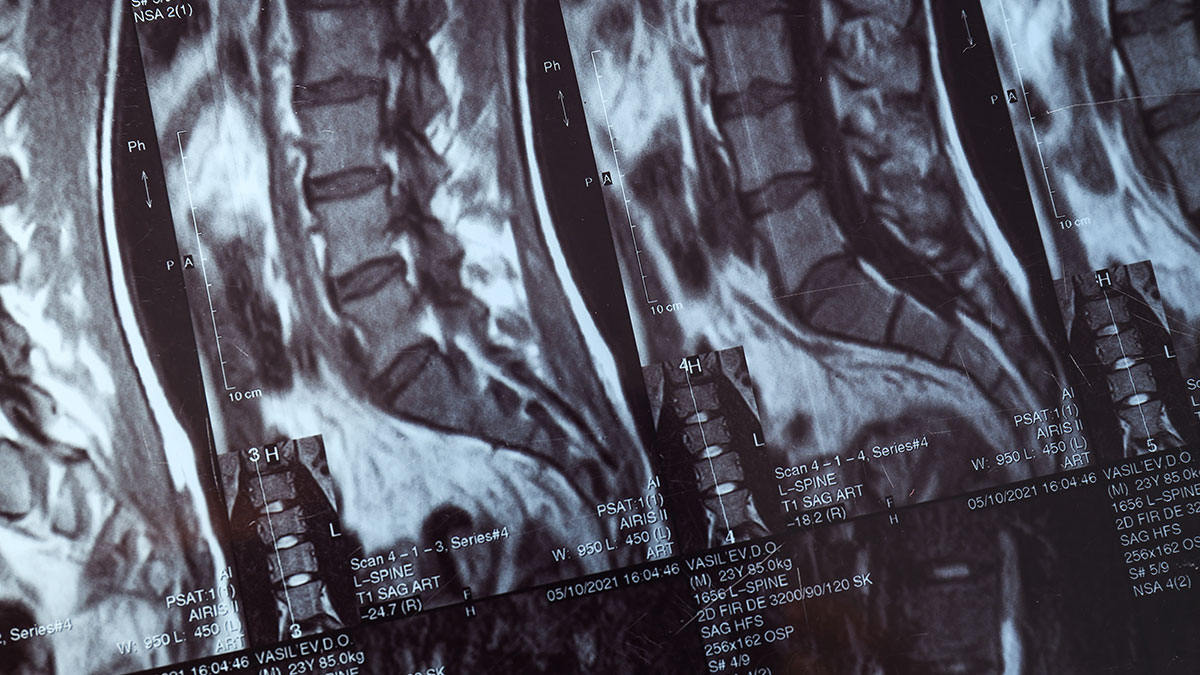

Il nostro team multidisciplinare affronta le patologie della colonna con un approccio olistico e multimodale, costruendo percorsi terapeutici personalizzati che accompagnano il paziente in ogni fase, dalla diagnosi iniziale fino al trattamento e alla riabilitazione funzionale.

Tecnologie AI in ambito rielaborazione dei dati di TC e RMN